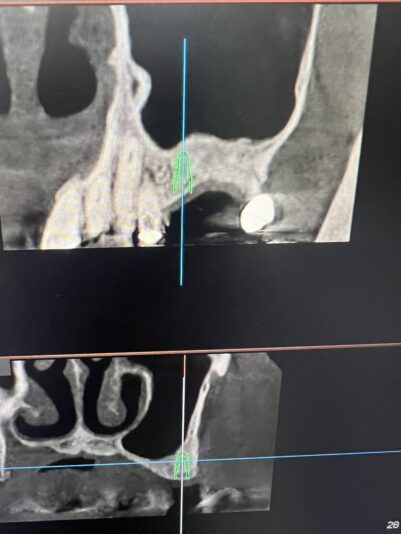

I have this implant case for tooth #28. I am worried about the anterior loop of the IAN here. It looks like it terminates at slice 62 and 63 but then I have a circular radiolucent area in slice 65. Do you think this is still the mental? If so I have about 10mm from the crest of the ridge. Do you think I’d be safe with an 8 mm implant here?

Just looking at what you provided it looks like there is sufficient room for an 8mm implant and that other slice I believe around 65 just looks like a void around the bone that looks similar to the pano version of the cbct and doesn’t present in other slices, nerve appears to be below that area.

Here are some screenshots of the CT for the case I am planning. Should I be concerned about the circular radiolucent area below 22 on page 2? When I traced it back I only saw it in a few segments. I remember Ivan saying there could be anterior branches of the IAN or vasculature in this region.